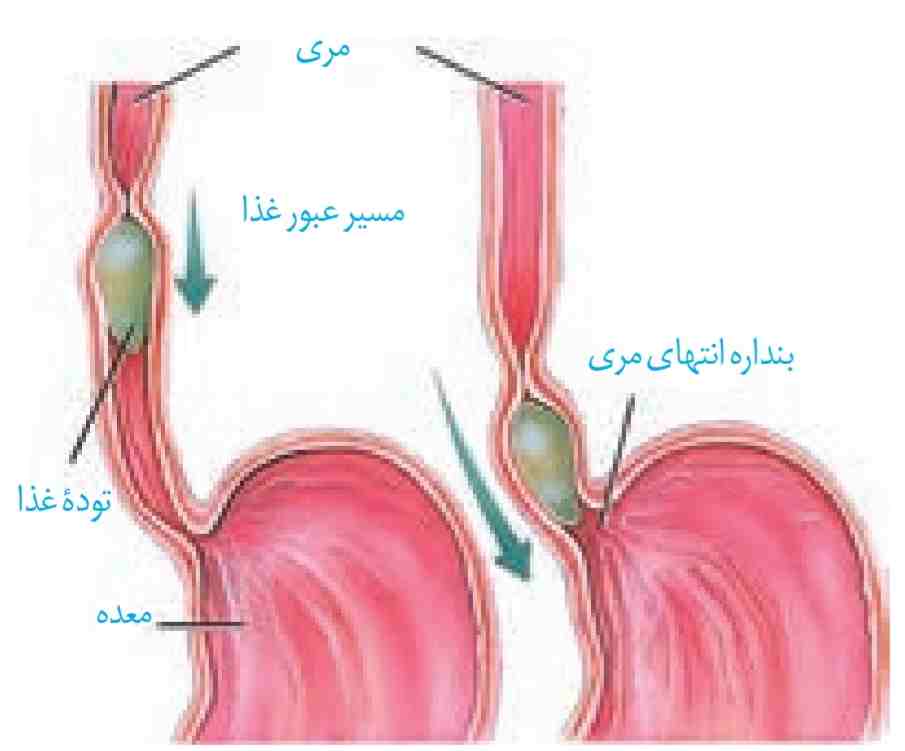

لولهٔ گوارش، لولهٔ پیوستهای است که از دهان تا مخرج ادامه دارد. در قسمتهایی از لوله گوارش ماهیچههای حلقوی به نام بنداره (اسفنکتر) وجود دارد. بندارهها در تنظیم عبور مواد نقش دارند (شکل ۲).

شکل ۲- بندارۂ انتهای مری

شکل ۲- بندارۂ انتهای مری

در ادامه دیوارهٔ ماهیچهای حلق منقبض میشود و حرکت کرمی آن، غذا را به مری میراند. حرکت کرمی در مری ادامه پیدا میکند و با شل شدن بندارهٔ انتهای مری، غذا وارد معده میشود (شکل ۷-ب). غدههای مخاط مری، مادهٔ مخاطی ترشح میکنند تا حرکت غذا آسانتر شود.

برگشت اسید معده (ریفلاکس): اگر انقباض بندارهٔ انتهای مری کافی نباشد، فرد دچار برگشت اسید میشود. در این حالت مخاط مری بهتدریج آسیب میبیند؛ زیرا حفاظت دیوارهٔ آن به اندازهٔ معده و رودهٔ باریک، نیست. سیگار کشیدن، الکل، رژیم غذایی نامناسب و استفاده بیش از اندازه از غذاهای آماده، تنش و اضطراب، از عوامل برگشت اسید معده اند.